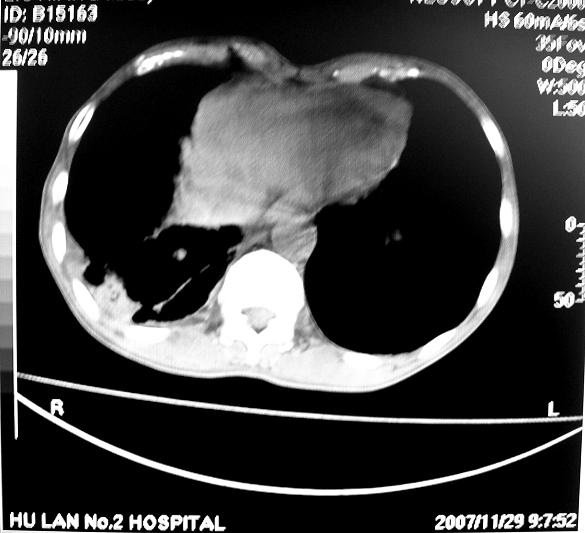

标题: CT10688:男63岁胸痛来诊

男63岁胸痛来诊

右肺病灶前缘不平整,略呈分叶状,其后方胸膜下脂线消失且似有向胸壁浸犯,左下肺球形灶内可见不规则空洞影,余双肺内可见多枚结节影,结合病史支持考虑肺癌肺内转移胸膜转移,便双肺后部病灶倒也是结核好发区域,建议穿刺活检

右下肺周围性肺ca并双肺及右侧胸膜转移。[emb6]

右下肺周围性肺ca并双肺及右侧胸膜转移。支持

右下肺周围性肺ca并双肺及右侧胸膜转移。

右下肺周围性肺ca并双肺及右侧胸膜转移。单看病变像炎性假瘤。

右下肺癌,双肺及胸膜转移

右下肺癌伴双肺及胸膜转移。

左肺病灶内可见空泡征及典型的胸膜牵拉征,不排除原发周围型肺癌的可能.